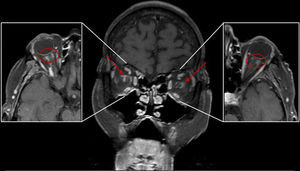

Se realiza una RM craneal y orbitaria (Philips Intera 1.5T) que muestra discreta leucoencefalopatía hipoxicoisquémica. Tras administrar gadolinio, en las secuencias T1 con saturación de grasa se observa realce orbitario perineural mal delimitado en la vaina de ambos nervios ópticos y en el tejido graso retrobulbar adyacente (figs. 1 y 2). Dicho hallazgo ha sido descrito en ACG con afectación visual, por lo que, en el contexto de la paciente, sin evidencia de otras patologías inflamatorias o neoplásicas, se sugirió este diagnóstico.

El hallazgo que se ha descrito con más frecuencia (menos de 10 casos en la bibliografía) es el realce perineural que afecta a la vaina del nervio óptico y a la grasa perineural (figs. 1 y 2), que sugiere cambios inflamatorios: perineuritis óptica1–4. En algún caso se ha descrito extensión hasta el quiasma (neuropatía óptica isquémica posterior5,6. En un paciente en el que se realizó biopsia perineural se confirmó tejido fibroadiposo con múltiples arterias con inflamación mural por linfocitos y células gigantes7.

Los hallazgos de la ACG en RM son poco frecuentes, inespecíficos y variables, lo que puede retrasar el diagnóstico y el tratamiento. Esta entidad puede provocar, con menor frecuencia, manifestaciones visuales por otras causas vasculares (oclusión de la arteria central de la retina, oclusión de arteria ciliorretiniana, infarto del lóbulo occipital)7. Sin embargo, una exploración de RM orbitaria de alta resolución, incluyendo secuencias STIR, T2 y T1 con saturación grasa y gadolinio intravenoso, puede demostrar captación perineural en una localización característica de NOIA que, en el contexto clínico adecuado, orienta hacia el diagnóstico precoz de ACG.